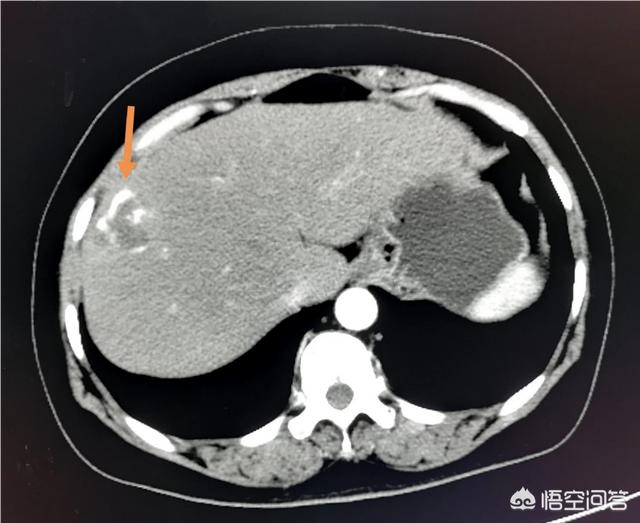

Par exemple, je suis médecin spécialiste de l'imagerie et je vois tous les jours des clichés de kystes hépatiques et rénaux. Lorsque j'examine ces films sur une longue période et que je viens pour un examen annuel, je constate que les kystes de nombreuses personnes restent fondamentalement inchangés, que certains d'entre eux peuvent avoir rétréci, que d'autres peuvent avoir grossi, mais qu'il est très rare qu'ils deviennent malins. L'observation à long terme a permis de constater que les kystes asymptomatiques peuvent être stables et inchangés.

En outre, si la tumeur est importante et présente des symptômes de compression, même si elle est bénigne, elle doit être enlevée chirurgicalement. Par exemple, si le kyste hépatique mesure plus de 5 cm, comprime le tissu hépatique environnant et présente des symptômes douloureux, il doit également faire l'objet d'un traitement chirurgical.

Par exemple, cet hémangiome hépatique de 2,5 cm est très courant et une échographie tous les 1 à 2 ans est recommandée.